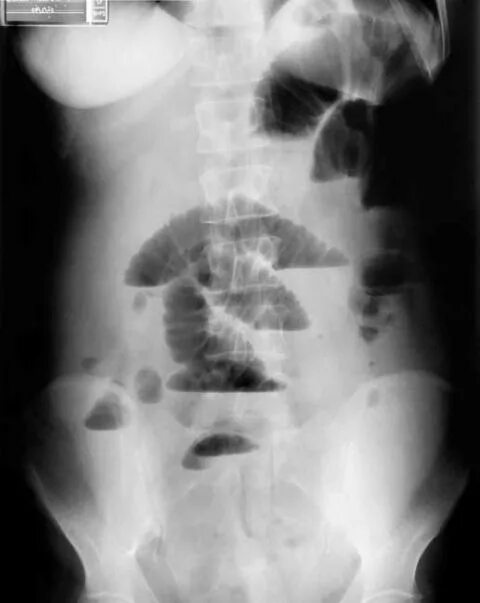

Симптом чаши